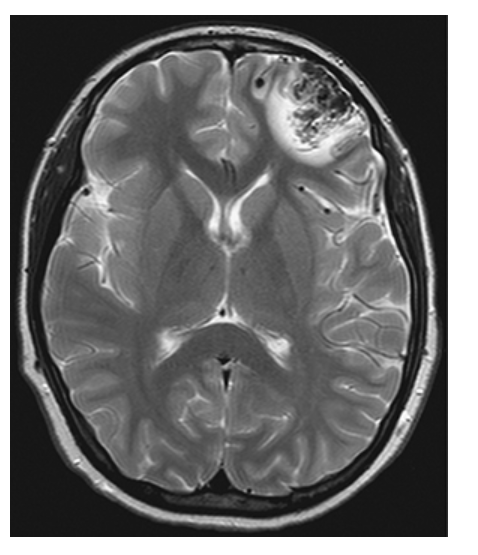

Brain Metastasis. Axial T2W image shows the left parietal mass with high central signal likely due to necrosis and high signal in the surrounding white matter due to vasogenic edema.